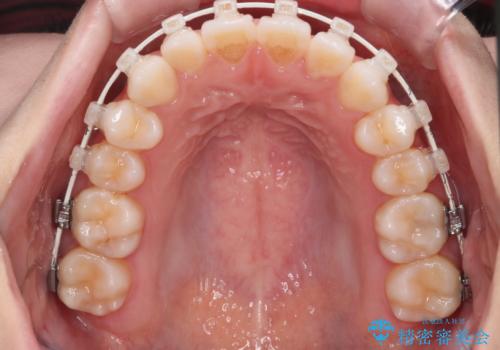

【審美装置】前歯で噛めない!抜歯しないで治したい

- 前歯の捻転とかみ合わせを主訴に来院されました。今回は抜歯をせずにIPRを実施し、並べる計画を立てました。

ワイヤー矯正を行いながら、顎間ゴムを患者さまにご協力していただき、短い期間で終了できました。